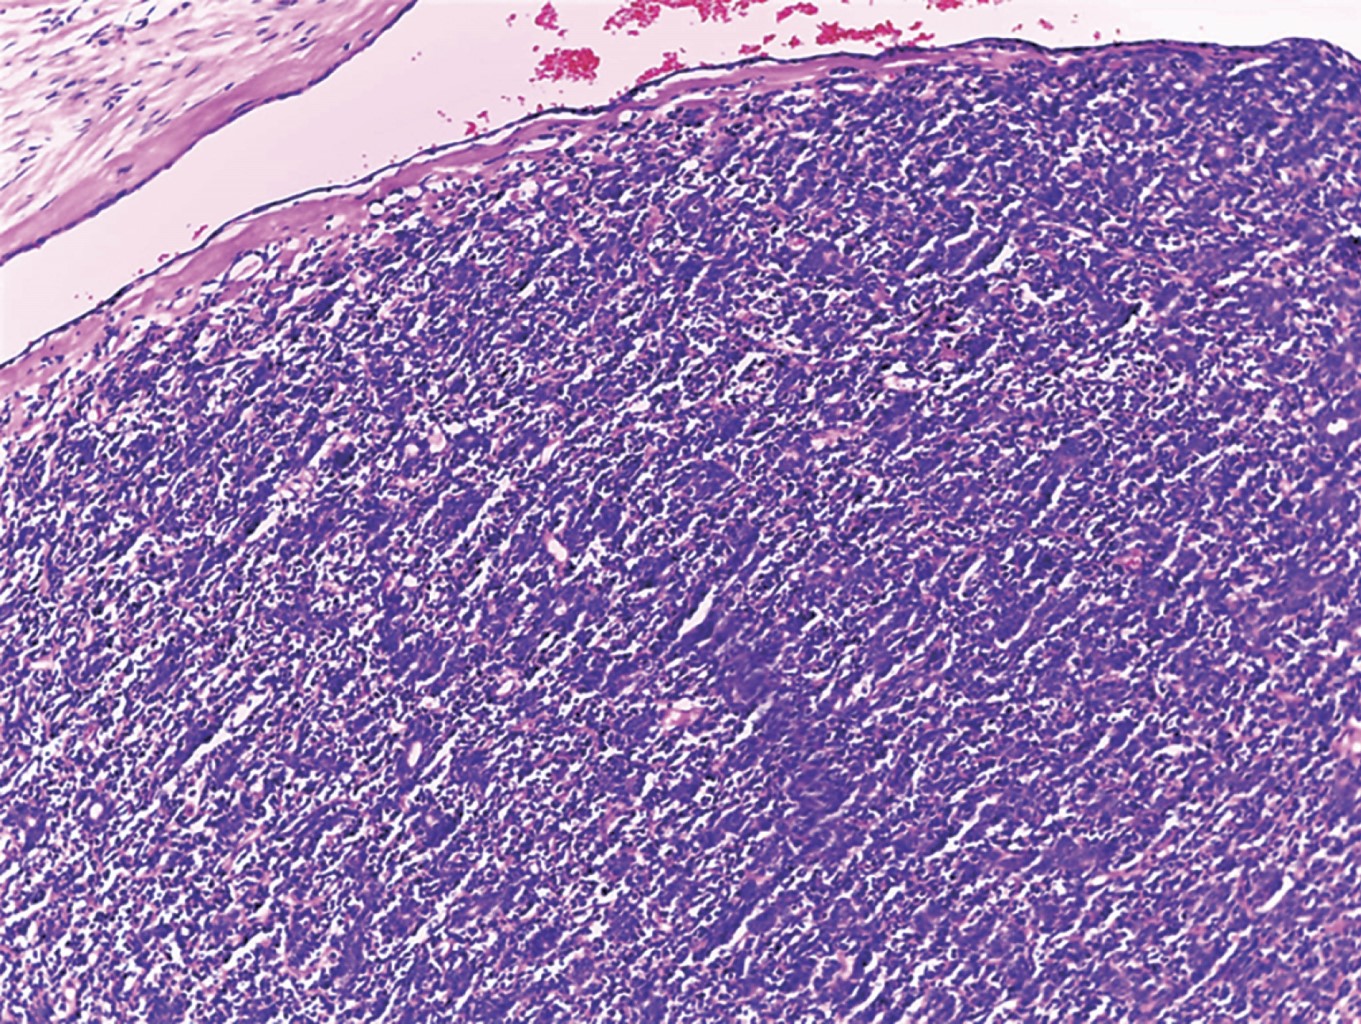

Figure 2